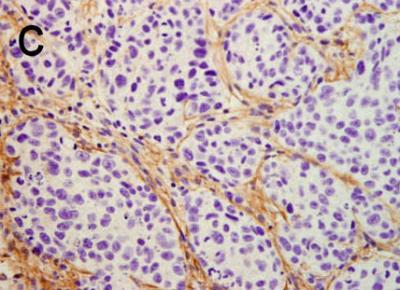

One of the conclusions highlighted in the study is that in the tissues examined, pancreas and brain, CPEB4 is not detected in healthy cells but only in tumor ones. Thus inhibition of this protein would provide a highly specific anti-tumor treatment and with few adverse effects, "one of the main drawbacks of many cancer therapies", says Pilar Navarro, a researcher specialized in pancreatic cancer.

Using experiments involving human cancer cells in mice, these researchers have demonstrated that the decrease in CPEB4 levels in cancer cells reduces the size of tumors by up to 80%. Although the study is limited to two kinds of tumor, according to the co-authors, "given the effects observed in the tumors examined and the type of genes regulated by this mechanism, it is expected to be involved in many other types of cancer".